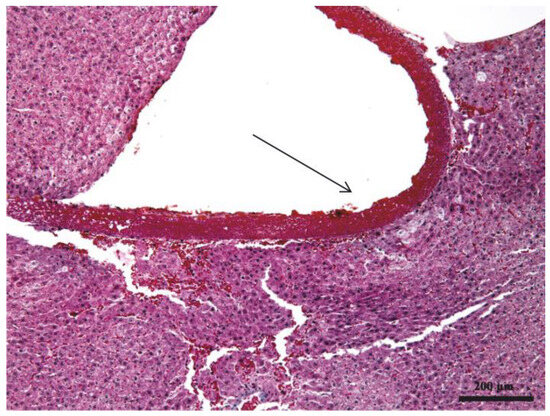

3.1. Histopathologic Results